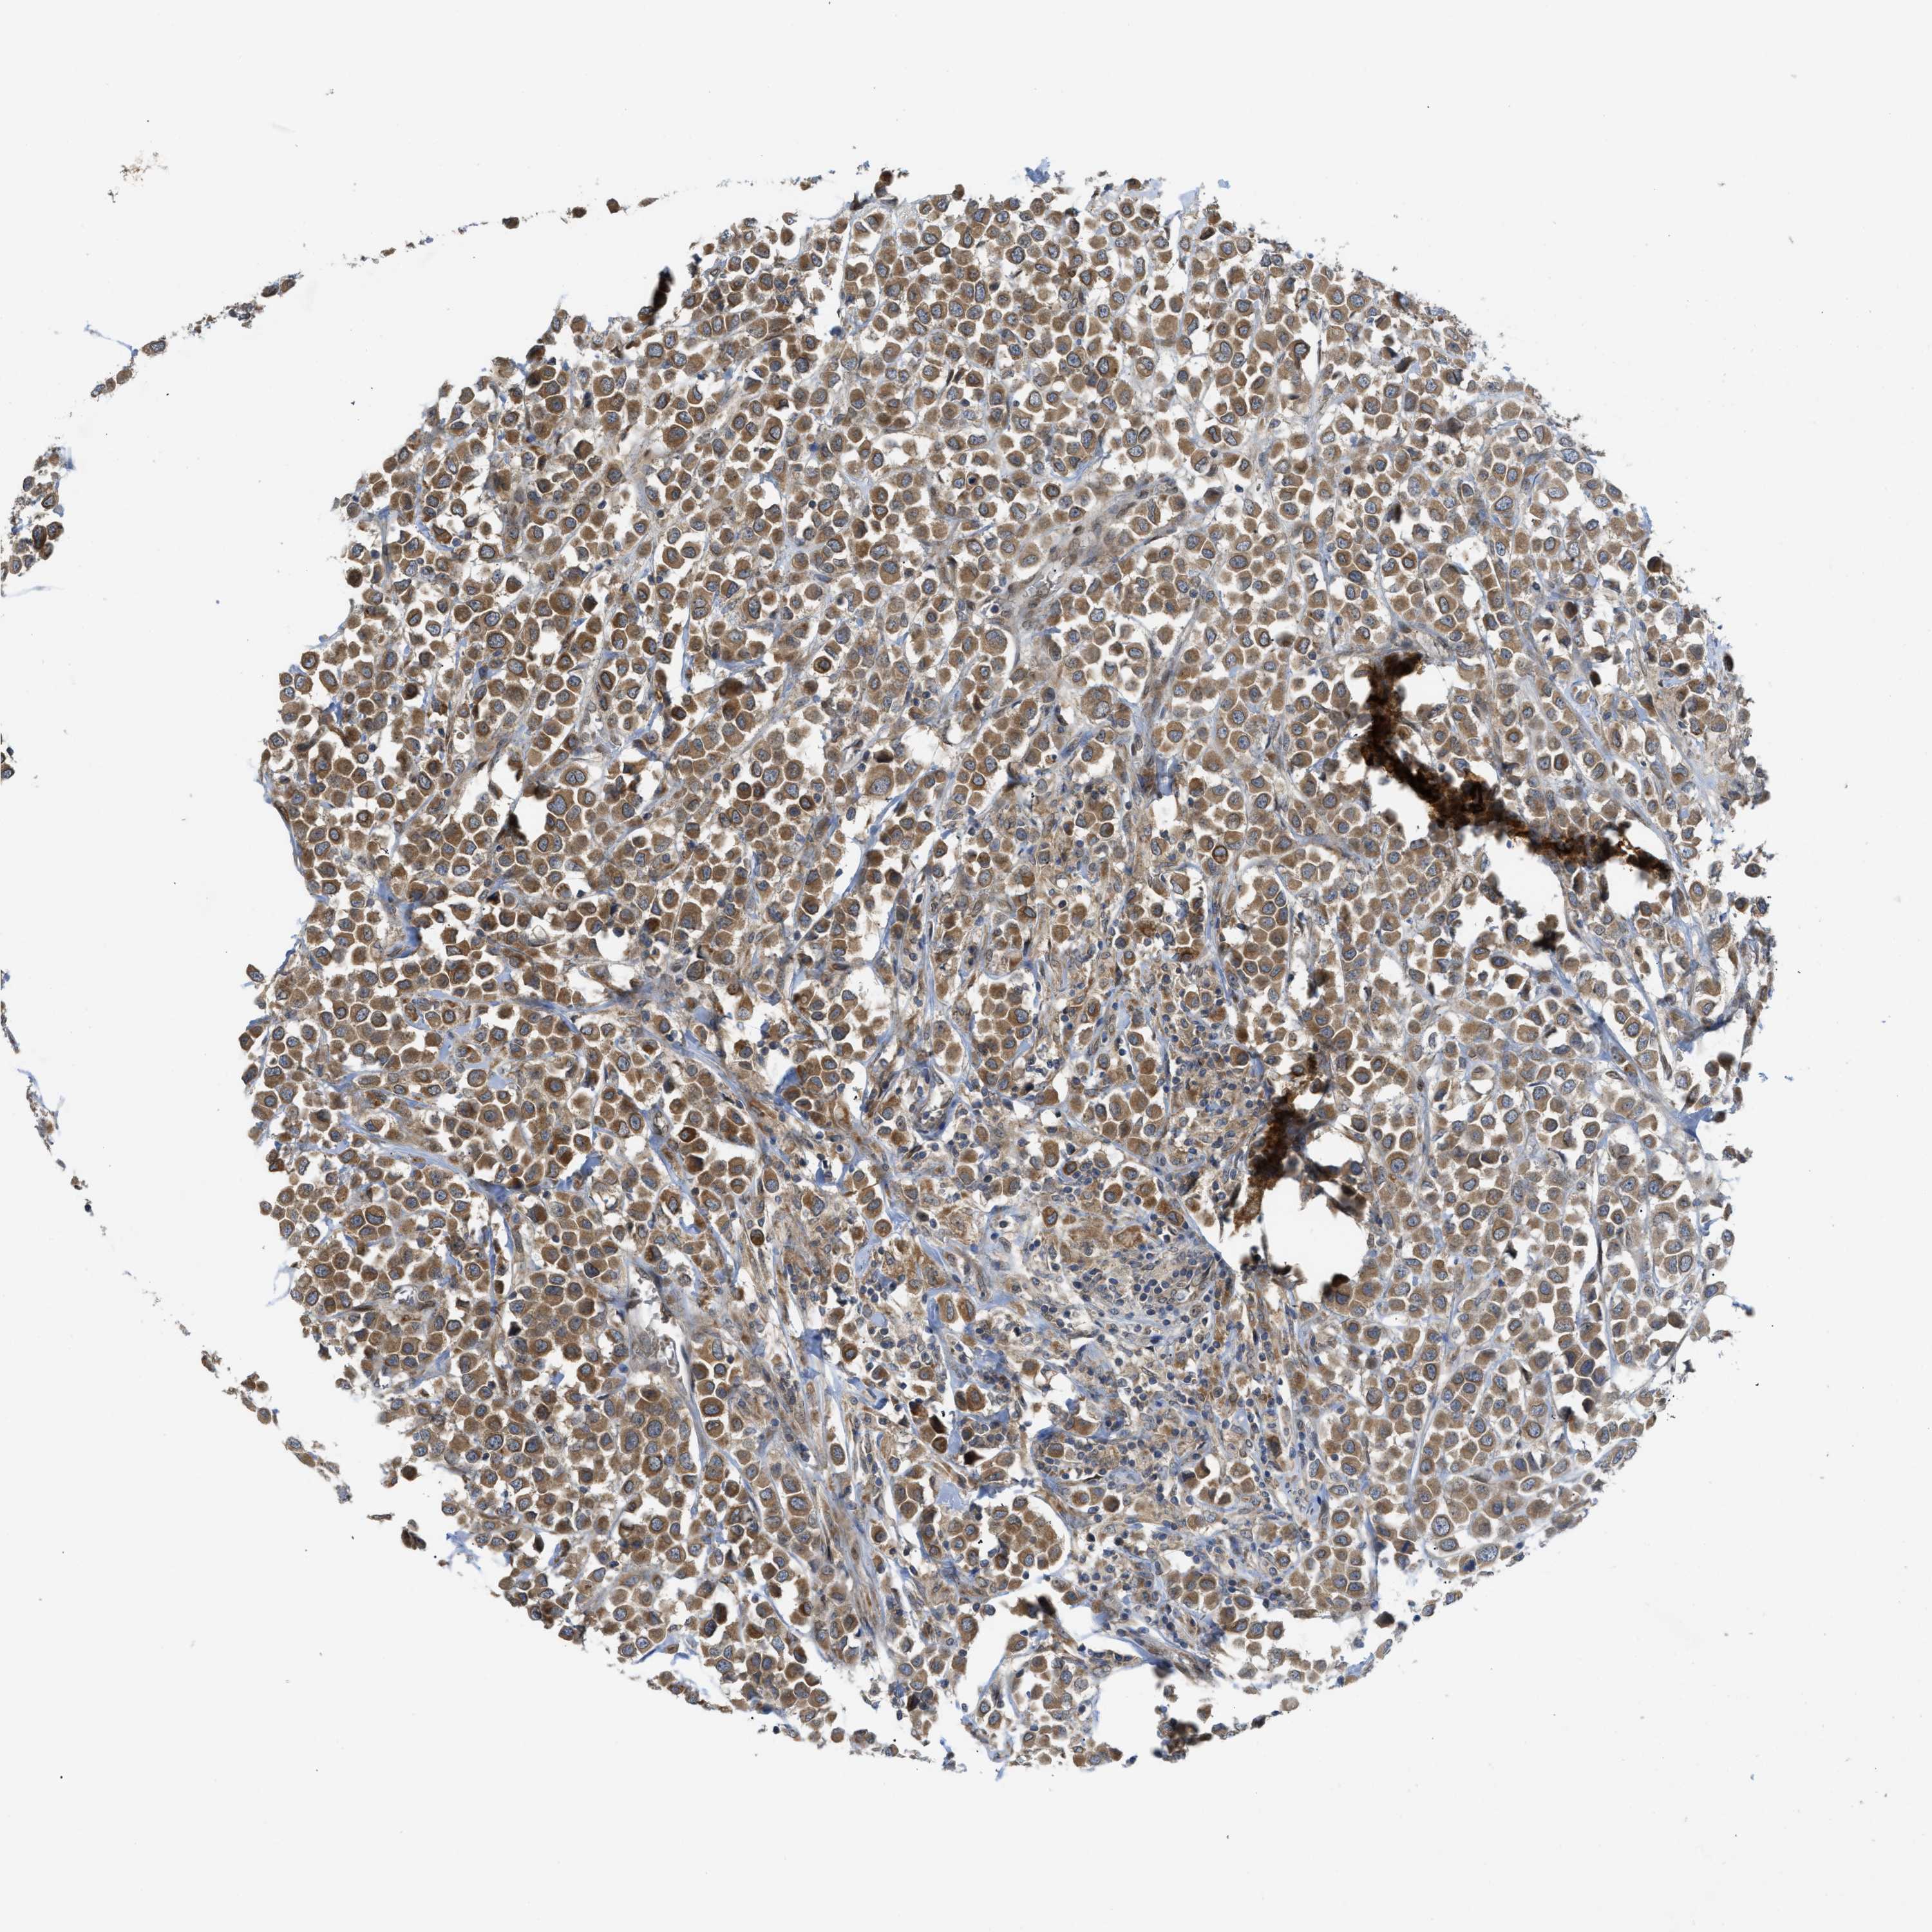

BRCA TCGA BRCA VALIDATION PROTEIN EXPRESSION

Breast cancer

Human cancer